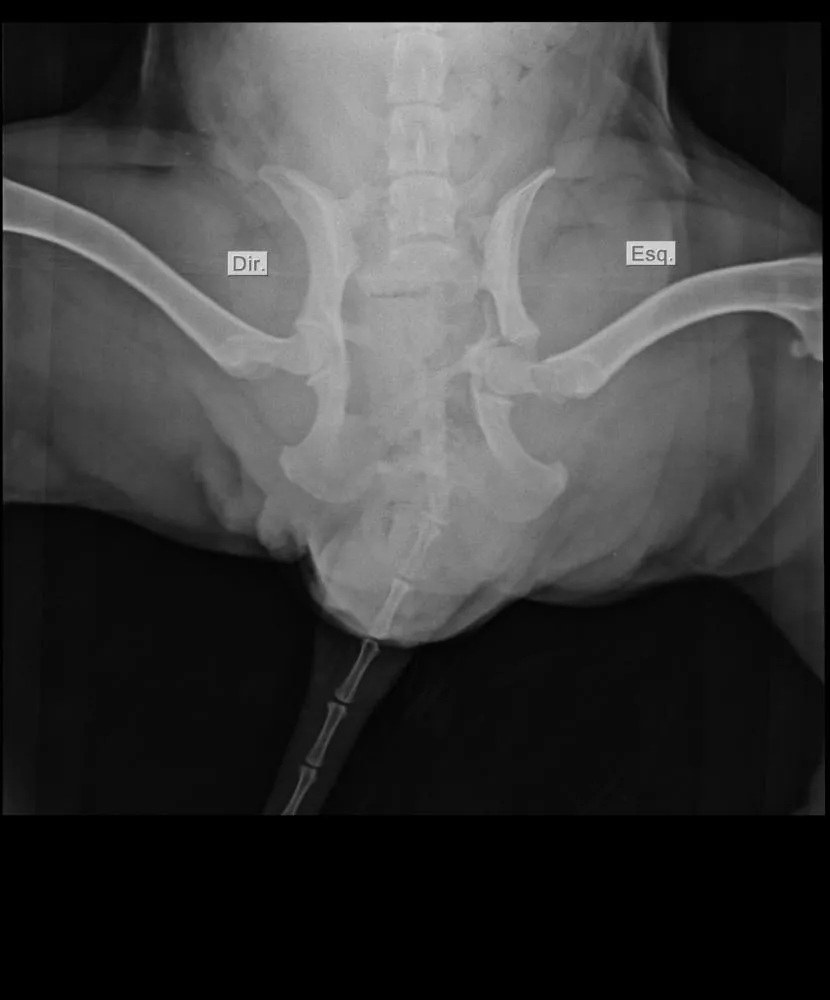

Brenda explicou que decidiu adotar a cadela, que vivia na rua, e que o animal foi atropelado na noite do dia 31 de dezembro, sofrendo fratura em um osso próximo à região pélvica, já que o condutor do veículo envolvido no atropelamento não prestou socorro.

“Ela fugiu de casa no dia 31 de dezembro, e nós a encontramos ainda no mesmo dia, depois de ser atropelada. A pessoa que atropelou não prestou socorro, e agora ela precisa passar por uma cirurgia de urgência, mas nós não temos condições de arcar com o valor do procedimento”, explicou Brenda.